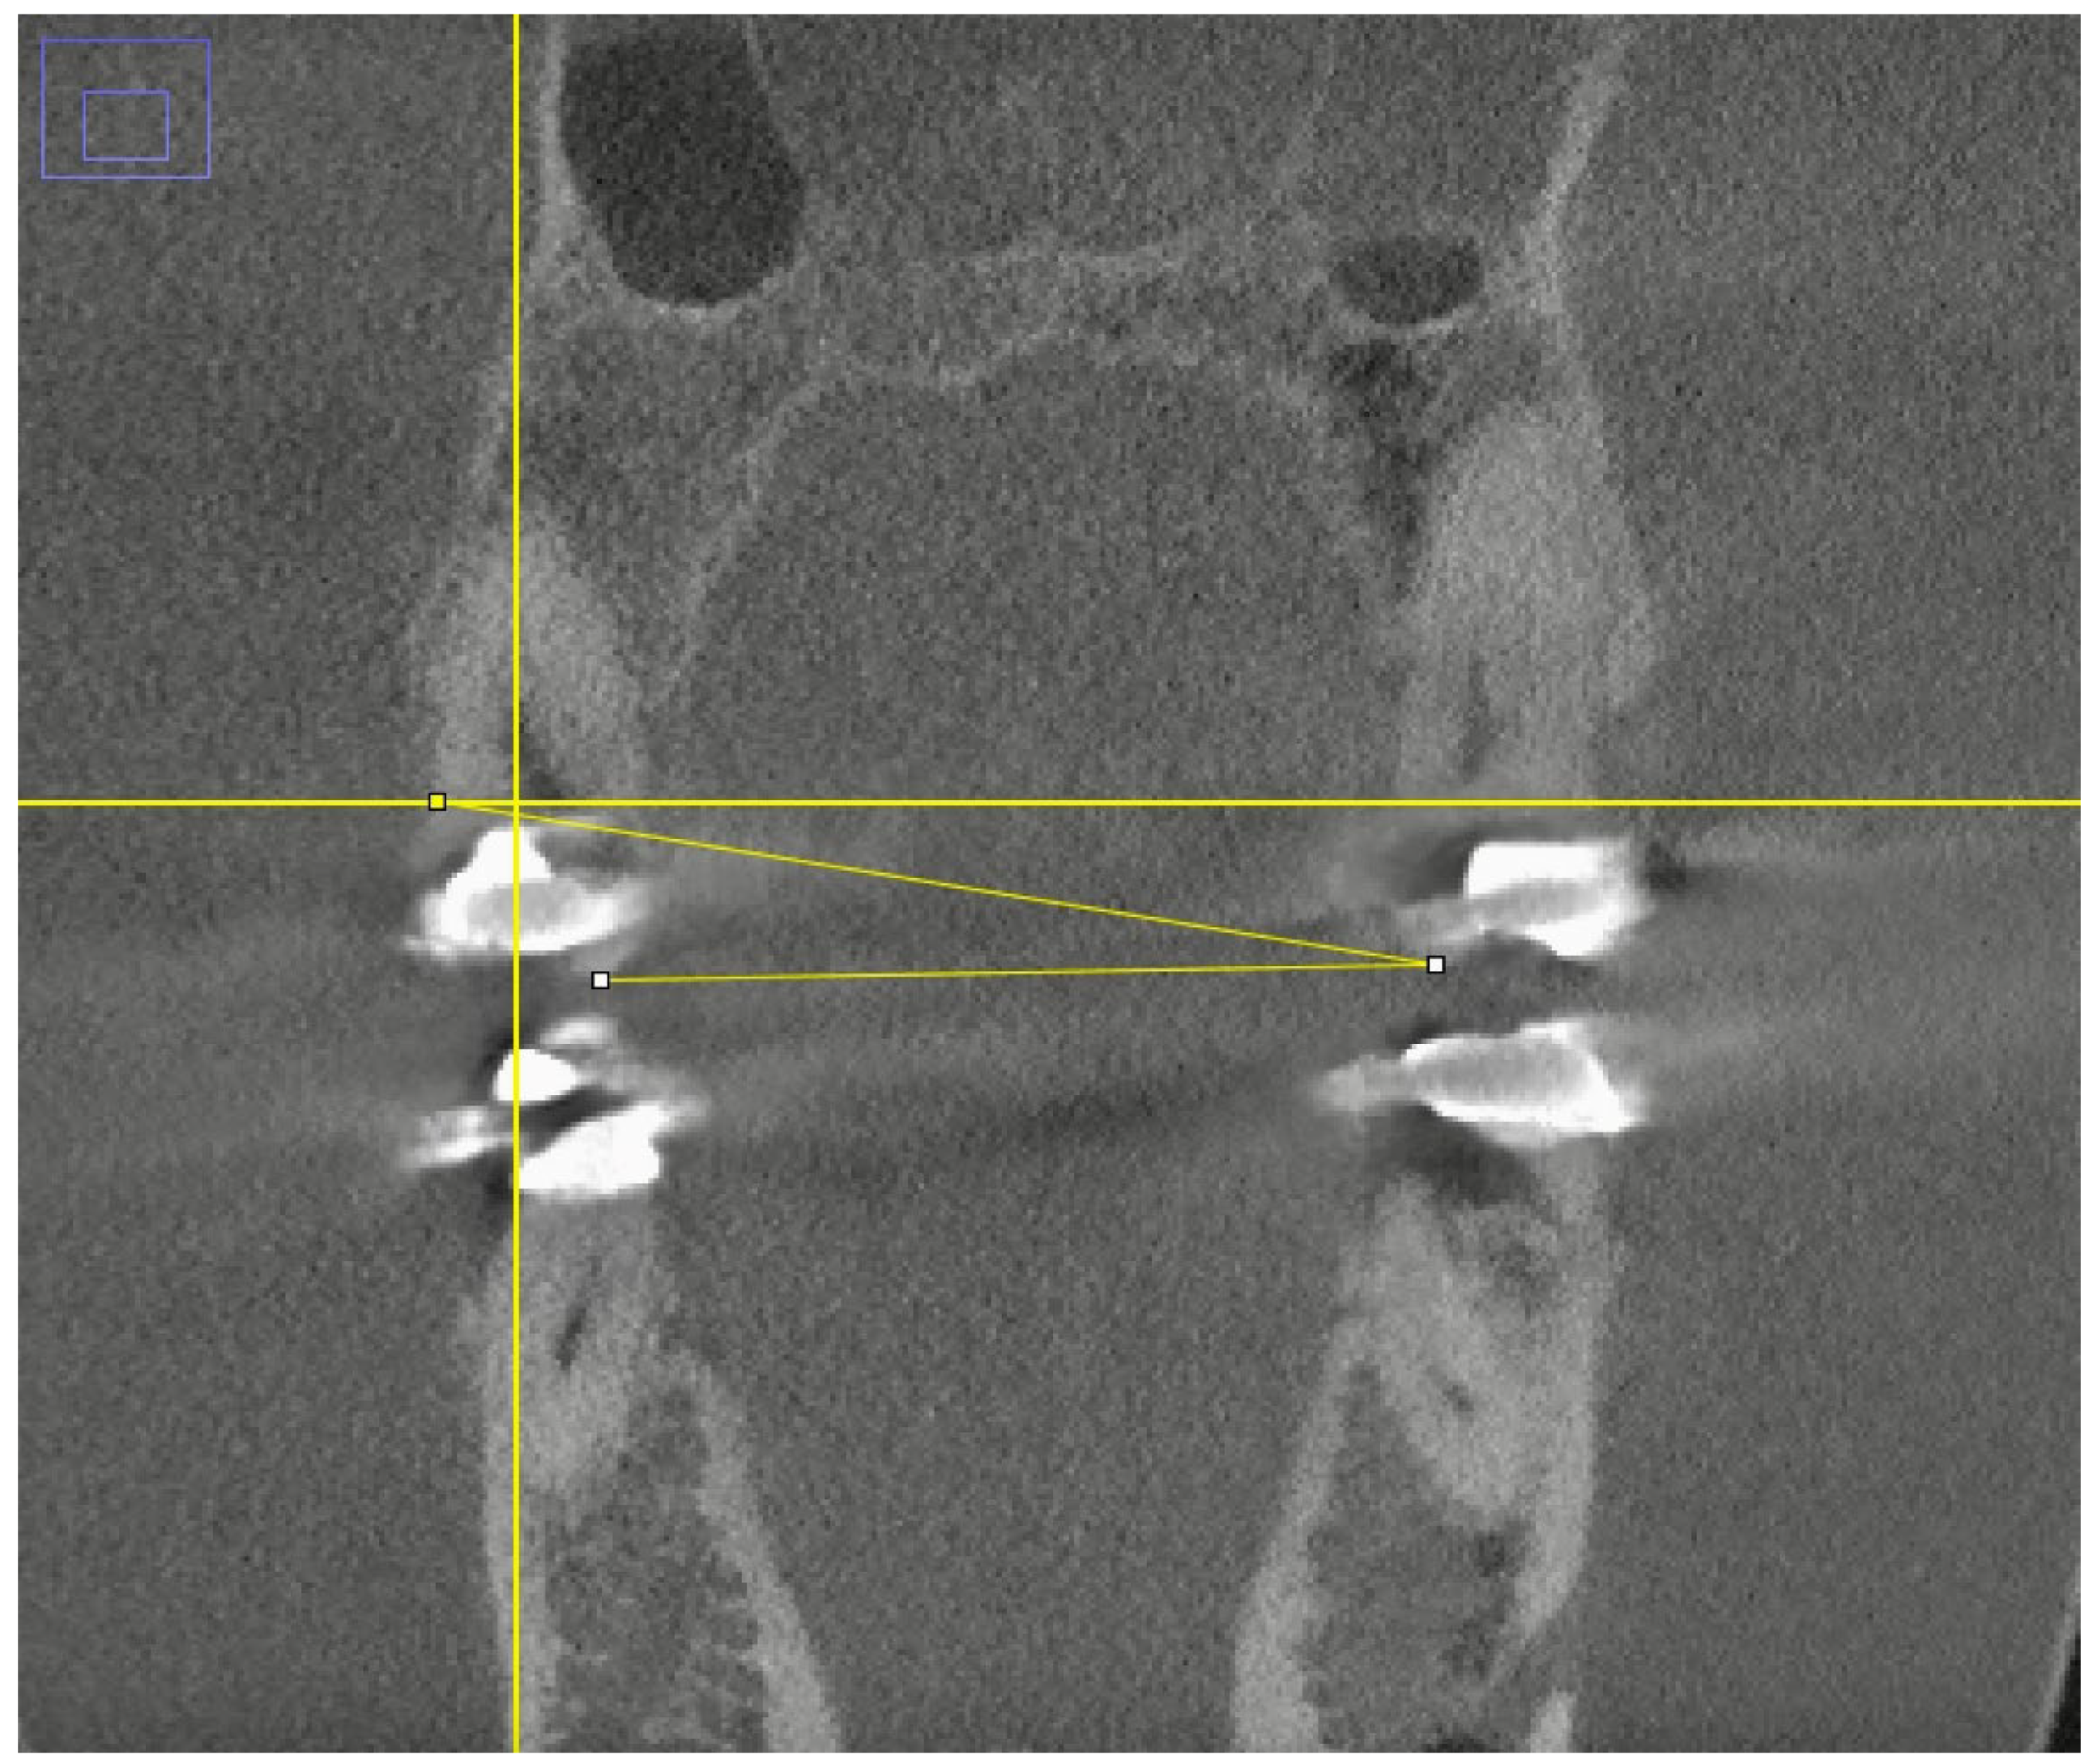

2. Materials and Methods

2.1. Image Acquisition and Experimental Setup

2.2. CBCT Preparation and Image Selection

2.3. Evaluation of Image Quality and Artifacts